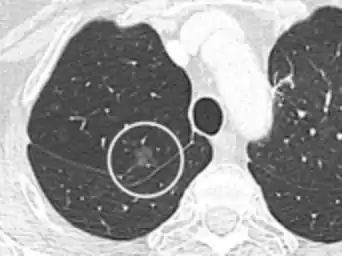

CT scan

For incidentally detected nodules on CT scan, Fleischner Society guidelines are given in table below. For multiple nodes, management is based on the most suspicious node.[8] These guidelines do not apply in lung cancer screening, in patients with immunosuppression, or in patients with known primary cancer.[8]